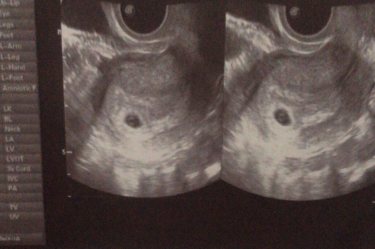

Вот мой малыш! Поставили 6 недель. Сказала что у меня живот болит. Говорят что угроза. Мне дали таблетки для сохранения ребёнка. До сих пор болит живот и спина.

Когда отслойка была тоже болела спина и живот